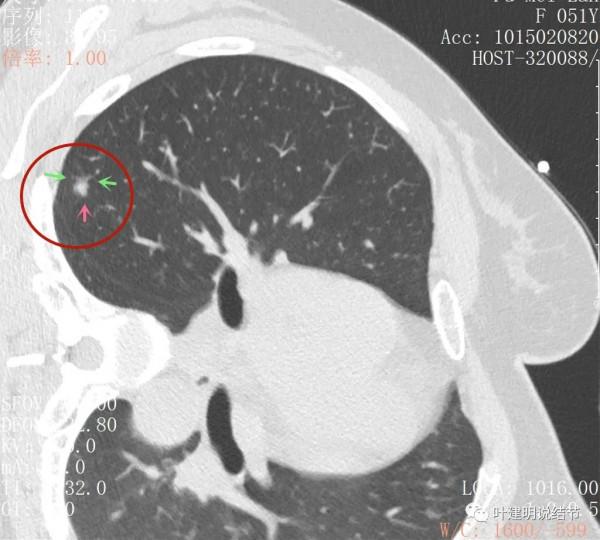

右肺上葉後段磨玻璃結節

感覺是混合磨玻璃,而且密度偏高

見邊緣不光整,似有細毛刺

整體輪廓清楚

有微血管徵

胸腔有輕微牽拉

從平掃看,病灶雖然小,但就不舒服,極可能是惡性的。我們再來看她其餘部位還有小結節:

上葉後段另有一磨玻璃結節,約5-6毫米許,密度低,瘤肺邊界清,考慮不典型增生或原位腺癌可能性大,但目前風險程度低

右上葉後段還有一微小結節,約1-2毫米,密度不高,瘤肺邊界清,考慮也是原位腺癌可能性大,目前風險程度低